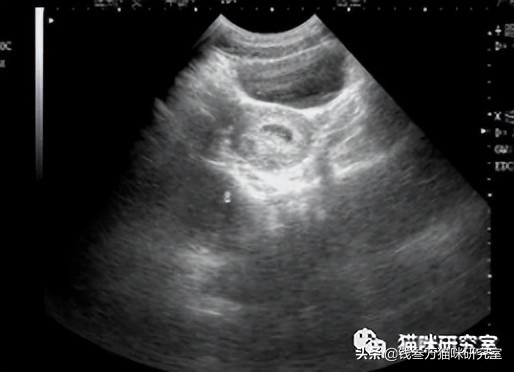

首先带一只怀孕的母猫去医院,按住,做B超:

医生通过B超图像,能测量出小猫的头围直径:

头围直径的单位是毫米mm。

然后套公式:头围 x 2.5 + 3 = 怀孕天数。

比如,头围测出来是23mm。

那么套公式:23mm x 2.5 + 3 =60.5 天

也就是已经怀孕了60.5天。